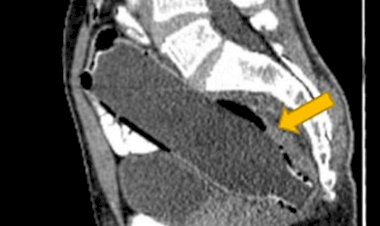

Esposa leva marido “constipado” ao hospital e médicos encontram...

A garrafa possuía 19 cm e foi inserida pelo paciente via retal. Incapaz de retirar...